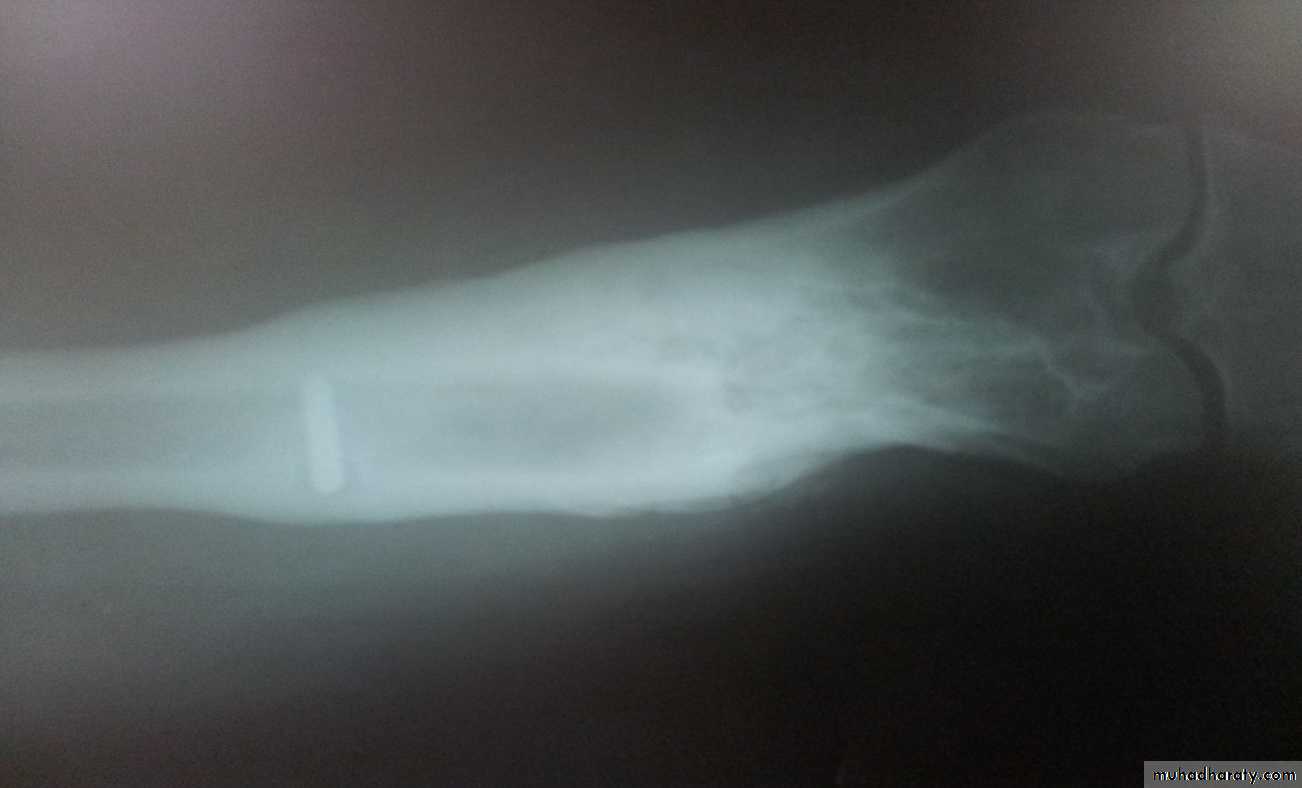

Chronic Osteomyelitis

It is used to be a sequel of acute haemtogenous infection, but now it is more frequently follows open fracture or postoperative complication.Pathology:

There is destruction of bone that follows acute infection leaving sequestra surrounded by dense sclerotic bone.

The imprisoned sequestra provoke a chronic seropurulent discharge, that escape through a sinus. Bacteria may remain dormant for years giving rise to recurrent flare of acute infection.

Imaging:

X-Ray: shows area of rarefaction surrounded by sclerosis.

And sometimes with sequestra.